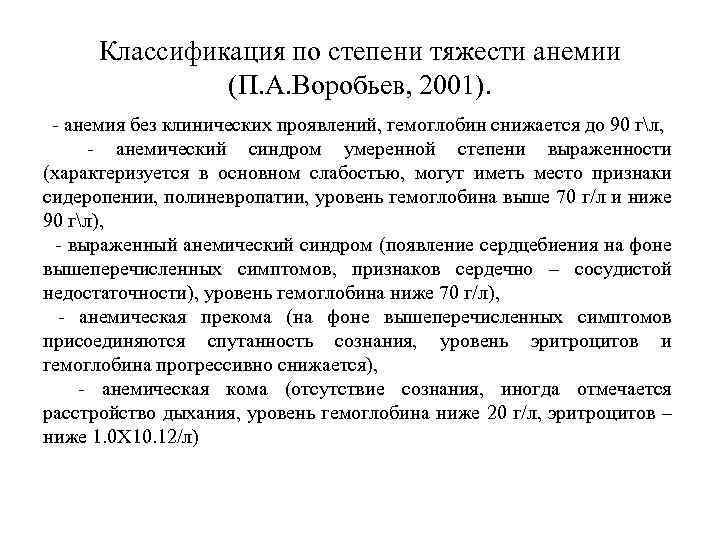

Классификация по степени тяжести анемии (П. А. Воробьев, 2001). - анемия без клинических проявлений, гемоглобин снижается до 90 гл, - анемический синдром умеренной степени выраженности (характеризуется в основном слабостью, могут иметь место признаки сидеропении, полиневропатии, уровень гемоглобина выше 70 г/л и ниже 90 гл), - выраженный анемический синдром (появление сердцебиения на фоне вышеперечисленных симптомов, признаков сердечно – сосудистой недостаточности), уровень гемоглобина ниже 70 г/л), - анемическая прекома (на фоне вышеперечисленных симптомов присоединяются спутанность сознания, уровень эритроцитов и гемоглобина прогрессивно снижается), - анемическая кома (отсутствие сознания, иногда отмечается расстройство дыхания, уровень гемоглобина ниже 20 г/л, эритроцитов – ниже 1. 0 Х 10. 12/л)